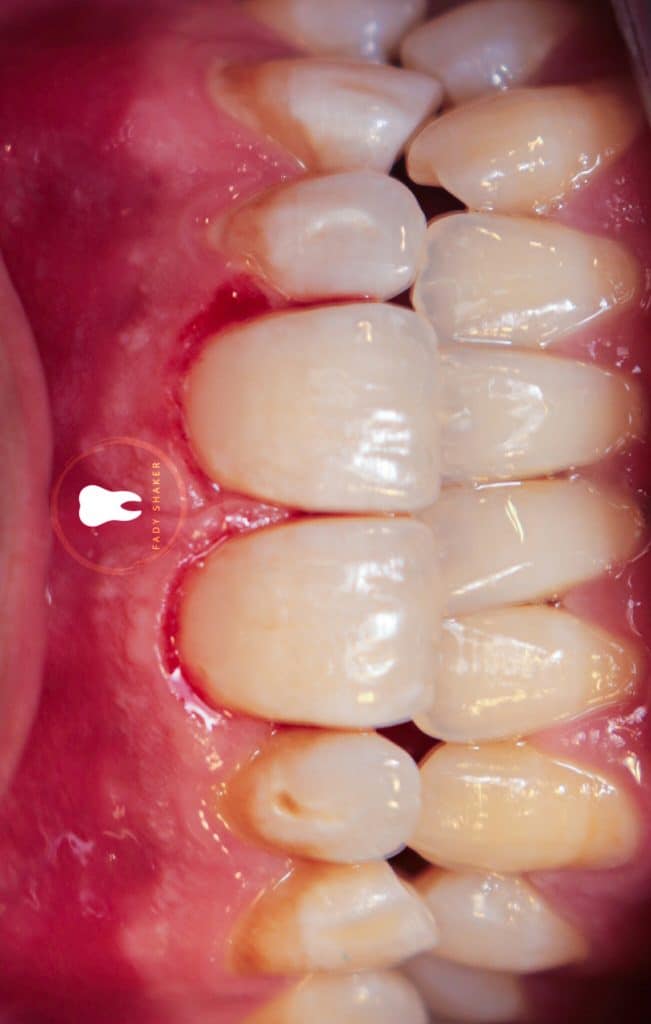

11- wait for 3mins for elimination of shrinkage stress within hybrid layer

12- apply dentin layer of composite and avoid contact of gingival margin to control C-factor

13- after that apply dentin layer on ginival margin

14- apply final enamel layer and cure it with pulse cure mode to delay postgel phase and allow composite to flow

15- finishing and polishing

16- immediate result & waiting for rehydration